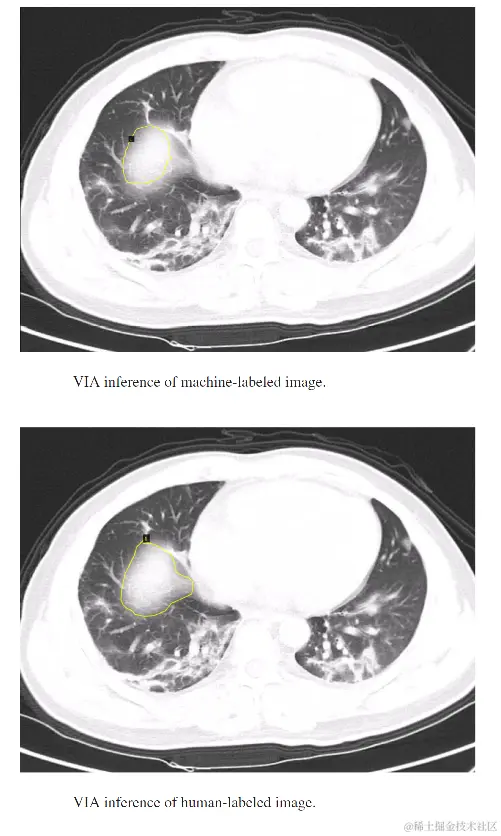

我们测试了我们的方法,目的是为Covid感染区域生成自动化的计算机标签。机器生成的标签和人类注释的标签的结果显示如下。可以看出,自动标注引擎生成的合成标签质量相当好,可以用来重新训练对象检测模型或生成更多的标注数据,可以用于不同的任务。

机器生成的标签与肺部CT扫描中Covid感染区的人类注释标签的比较,[图片改编自&版权:doi: 10.1109/TEM.2021.3094544。经许可转发] 。